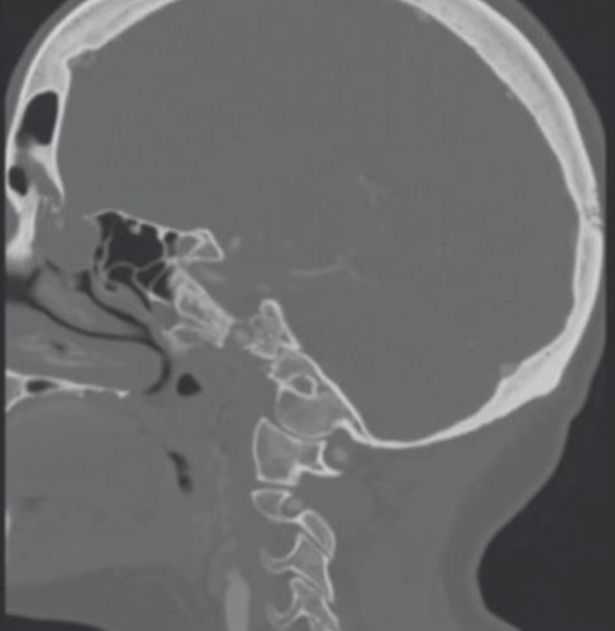

Το σημείο που έσπασε το οστό

Τα οστά του κρανίου στο σημείο εκείνο ήταν σπάσει ελαφρώς με αποτέλεσμα τα εγκεφαλικά υγρά να τρέχουν στην μύτη.

Προφανώς, εκείνος που έκανε το τεστ έβαλε την ειδική μπατονέτα πάρα πολύ βαθιά με αποτέλεσμα να δημιουργήσει μια μικρή τρύπα στον εγκέφαλο της άτυχης γυναίκας.